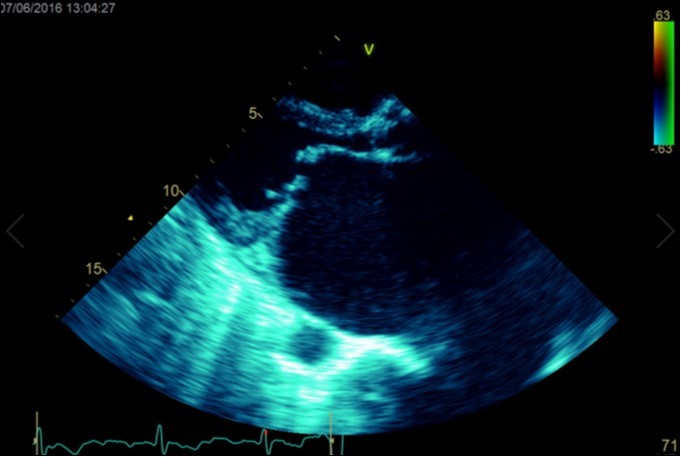

A dramatically dilated left atrium was seen on a TTE (see Figure 2a, Figure 2b, Figure 2c, and Figure 2d). Severe mitral stenosis with associated regurgitation was evident, with a mean gradient across the valve of 11mmHg and a hyperdynamic left ventricle. The left atrial volume measured by Simpson’s biplane method (see Figure 2c) was 2108mL, or 1548.5 ml/m2, based on height 1.55 metres and weight 44 Kg. Normal left atrial volume in a woman is 16 - 34 ml/m21. The computed tomography scan (CT) chest AP view (see Figure 3) is also shown.

Figure 2d.Transthoracic echocardiogram Apical 2C view. Left atrial size estimation by Simpson’s biplane method from apical 2C view. Severely enlarged left atrium (estimated 2108ml, 1548.5ml/m2)

Massive left atrial dilatation is a recognized phenomenon in chronic mitral stenosis, and is considered by some to be protective against the development of pulmonary oedema in mitral regurgitation 2. Left atrial dilatation to this extent is not usually seen in living patients, however. The largest described left atrium was 3000 ml at autopsy, with another measuring 1760 ml at autopsy in 19313. Other reports in living patients include a left atrium that was estimated at approximately 2000ml on magnetic resonance imaging 4.The more precise measurements for the left atrial size we recorded on cardiac ultrasound have not been described previously. Considering the size of the left atrium, it is surprising that the mean gradient across the mitral valve was only 11mmHg. Although this is certainly severe, it could be expected that a gradient would be higher based on the severity of the left atrial dilation. We hypothesize that the gradient may have been greater previously, however the massive dilation of the left atrium may have subsequently led to a dilation of the mitral annulus, leading to an improvement in the mitral valve effective orifice area, and hence a reduction in the severity of the mean mitral valve gradient.